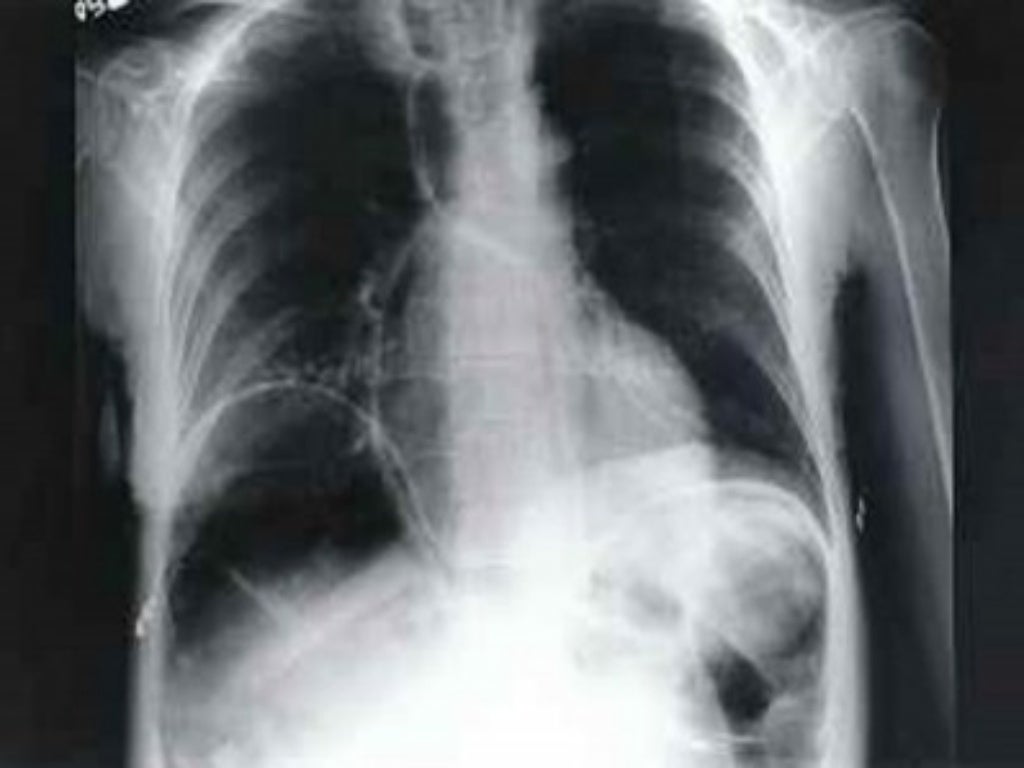

Free gas is seen below the diaphragm on plain chest roentgenogram taken Gas Below Diaphragm But the presence of haustration or valvulae. However, if gas builds up in the intestines, it can be painful. Gas pain in the chest can result from digestive problems or swallowing air, and dietary changes can help get rid of it. Passing gas is a typical part of the digestion process. The chilaiditi sign is often confused with pneumoperitoneum, which. Gas Below Diaphragm.

Chest radiograph demonstrating free intraabdominal air Openi Gas Below Diaphragm This is a sign of bowel. Pneumoperitoneum (aeroperitoneum is a rare synonym 12) describes gas within the peritoneal cavity, often due to critical illness. Gas pain in the chest can result from digestive problems or swallowing air, and dietary changes can help get rid of it. The chilaiditi sign is often confused with pneumoperitoneum, which usually requires urgent abdominal surgery.. Gas Below Diaphragm.